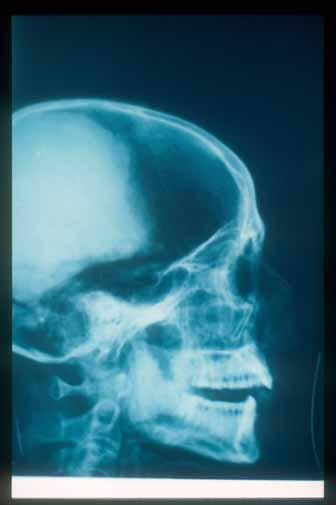

Lateral head x-ray of Rameses III.

KV 11: Rameses III, Burial chamber J, sarcophagus

Valley of the Kings, East Valley

West Bank, Luxor